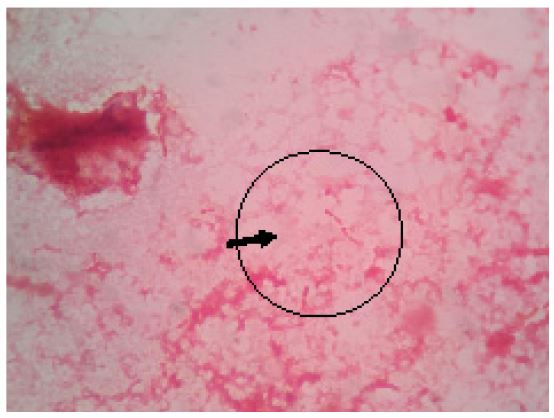

Figure 1: Roseomonas gilardii on Gram stain from culture plate (Pink, coccoid, vacuolated cells).